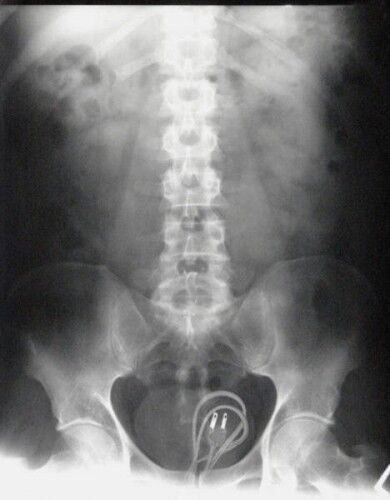

Röntgen Filminde İnsanların İçinden Çıkan Acayip Maddeler

1 / 9